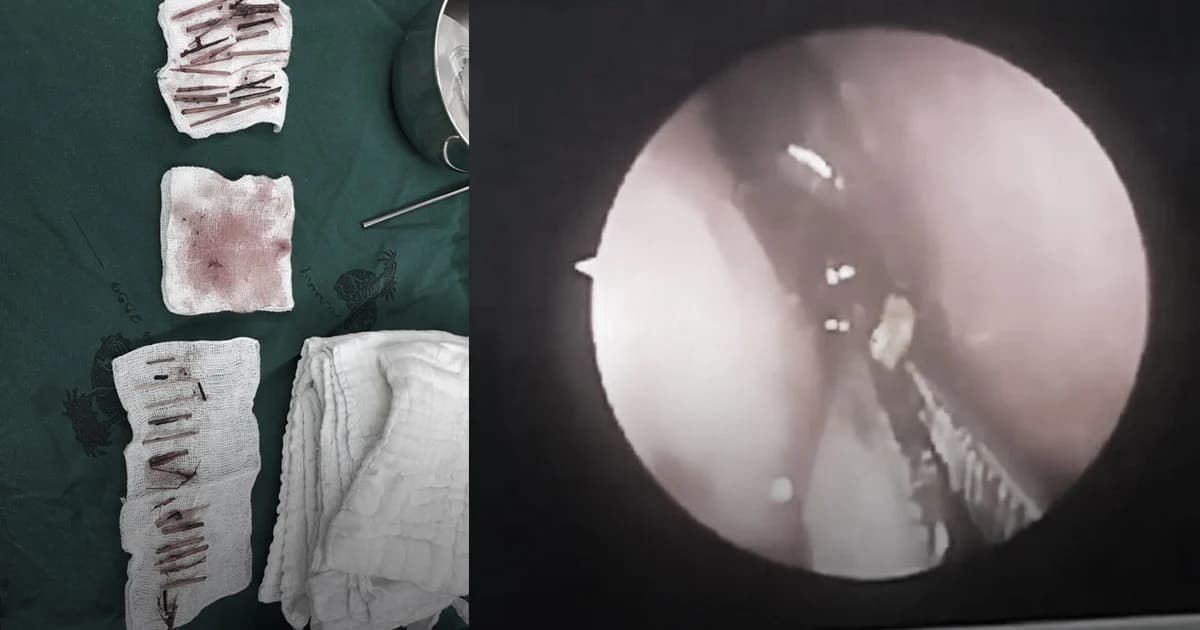

ผู้สื่อข่าวรายงานว่า เมื่อวันที่ 14 เม.ย.62 นายแพทย์อารักษ์ วงศ์วรชาติ ผอ.รพ.สิชล อ.สิชล จ.นครศรีธรรมราช โพสต์เฟซบุ๊กชื่อ “Arak Wongworachat” ระบุข้อความว่า “เมื่อสัปดาห์ที่แล้ว ผู้ป่วยชายอายุ 46 ปี ญาติพบว่าเมื่อเข้าใกล้จะมีกลิ่นเหม็นเน่า ลมหายใจกลิ่นแรงมาประมาณ 1เดือน คิดว่าเป็นโรคภูมิแพ้ หรือไซนัสอักเสบ จึงตัดสินใจพามาโรงพยาบาล แพทย์เวรตรวจพบว่าในจมูกมีหนองไหลจึงส่งปรึกษาหมอหู คอ จมูก ส่องกล้องเข้าไปดู พบมีไม้เสียบในรูจมูก จึงเซ็ทเข้าห้องผ่าตัด เพื่อดมยาสลบสิ่งที่เอาออกมาน่าตกใจมากครับ มีเศษไม้สั้นบ้างยาวบ้าง กว่า 40 ชิ้น มันเข้าไปอยู่ได้อย่างไร?”

กรณีรายนี้ก็เช่นเดียวกัน ตอนมาที่ รพ.สิชล พบแพทย์ที่ห้องฉุกเฉิน และแพทย์สังเกตว่ามีสิ่งผิดปกติในโพรงจมูก ตรวจพบหนองไหลออกทางจมูก แต่ไม่เห็นว่ามีเศษไม้ เพราะผู้ป่วยไม่สามารถบอกได้ว่าเกิดอะไรขึ้น กระทั่งส่งแพทย์เฉพาะทาง หูคอจมูก แต่ผู้ป่วยก็ไม่ให้ความร่วมมือ จนต้องให้ผู้ป่วยอดอาหาร ให้น้ำเหลือและใช้วิธีการดมยาสลบ จากนั้นใช้กล้องส่องเข้าไปดูในโพรงจมูก พบว่ามีเศษไม้หลายขนาด จึงใช้อุปกรณ์คีบออกมาพบเศษไม้เยอะมากกว่า 40 ชิ้น จากนั้นแพทย์ทำการผ่าตัดรักษาจนหายเป็นปกติ